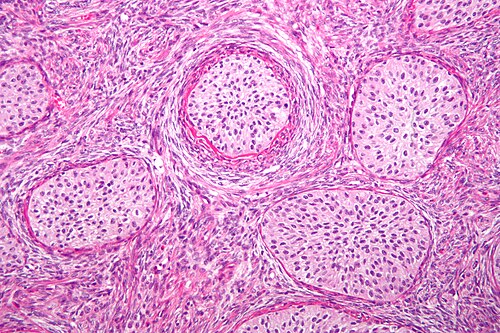

46 year old man/woman, asymptomatic, incidental finding

Ovary

Low magnification. H&E stain.

This is benign. The nests remind me of urothelium -- but it isn't urothelium.